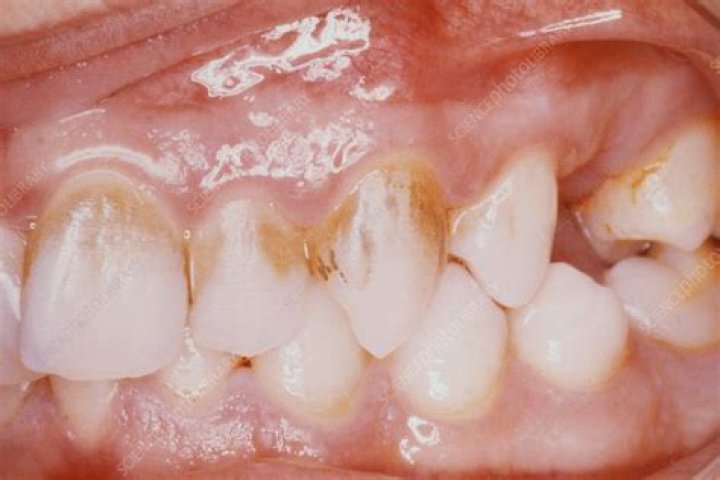

Chromogenic bacteria Baby teeth can develop a type of bacteria that causes brownish to black extrinsic stains on the surface of teeth. This discolouration usually goes away when permanent teeth come in but if it does not disappear then you should get your child to a dentist.

Chromogenic bacteria were proposed as an etiological factor in the production of black pigment. Periodontal pathogens such as Porphyromonas gingivalis, Prevotella intermedia, and Prevotella nigrescens are reported to be black-pigmented anaerobes in oral cavity[13].

Among all oral diseases, teeth infection is a commonly encountered problem in dentistry with teeth blackening commonly seen in kids. One of the major causes of teeth blackening are the chromogenic bacteria which form biofilm in the teeth. So far there is no significant and safe treatment available for teeth blackening.